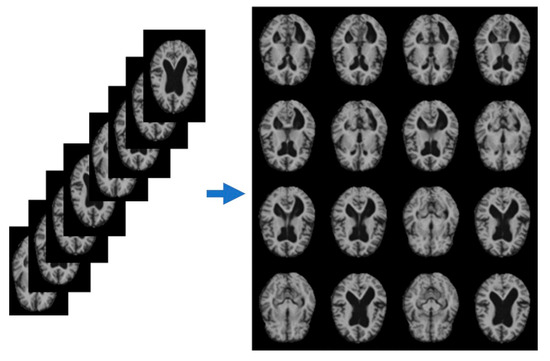

Data augmentation techniques were applied to increase the dataset size and variety, utilizing the Keras framework from TensorFlow-2.7.0 [25]. This involved geometric transformations such as flipping, rotating, shifting, and zooming, as shown in Figure 3. These transformations diversified the training dataset, improving the generalization capabilities of the machine learning models, reducing the risk of overfitting, and enhancing the models’ ability to learn meaningful features from the MRI data. The total number of images increased to 11,509, with 3198 CN, 2126 AD, and 5735 MCI images. The pre-processed and augmented images were stored in PNG format.

Figure 3. Transformation of images after augmentation, from left to right: original image, flipped, zoomed, shifted, and rotated.